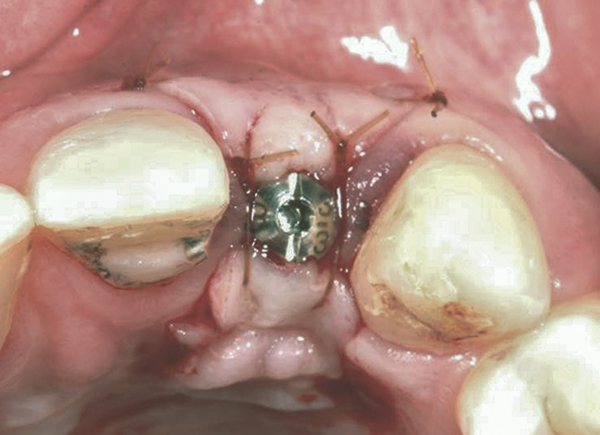

Fig 7. Vertical releasing incisions sutured to attain primary closure, buccal view.

Figure 7

In the esthetic zone it is preferable to avoid elevating papillae because flap elevation may induce recession and create unesthetic black triangles.4 If a flap is necessary to perform a procedure in an edentate area when adjacent teeth are present, the following technique can be used to circumvent blunting papillae. Make a horizontal incision along the midcrestal or palatal aspect of the ridge and terminate the incision 1 mm from the adjacent teeth (Figure 1). The incision is created palatally if it is desired to transpose keratinized tissue to the buccal. From the horizontal incision, create bilateral buccal vertical releasing incisions that extend obliquely at an angle (Figure 2). The vertical incisions can also be extended palatally (for access), but this is not always necessary (Figure 3). Preserved papillae contain gingival supracrestal fibers that subsequently help maintain papillary height (Figure 4). The distance the incision is extended vertically on the buccal is dictated by the task to be accomplished (eg, implant insertion only requires short vertical incisions, while bone grafting needs longer incisions) (Figure 5 and Figure 6). At the end of the surgical procedure, the severed papillary segments are sutured to their retained counterparts (Figure 7 and Figure 8). Figure 1 through Figure 8 demonstrate a submerged implant protocol.

Suturing—

A 5-0 chromic gut suture with a half round needle is very effective for suturing vertical releasing incisions, especially when the tissue is thin. The needle should engage 2 mm to 3 mm of tissue, and the sutures should be placed every 3 mm to 5 mm. However, do not suture the pedicle to the retained papillary segment, because the tissue is too thin. Sutures should be snugged down but not pulled too tightly, otherwise they can cause pressure necrosis. Movable tissue should be sutured to fixed tissue, and sutures should not be directly suctioned.